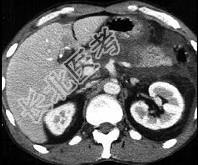

- 单项选择题女,45岁, 急性上腹部持续性疼痛10小时,程度剧烈, 放射到胸背部,恶心、呕吐, 白细胞计数增高,血尿淀粉酶升高, 影像所见如图,最可能的诊断是 ( )

A、急性单纯性胰腺炎

B、急性出血坏死性胰腺炎

C、慢性胰腺炎

D、胰腺癌

E、胰腺脓肿